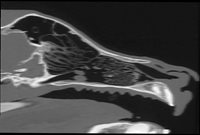

Bulles tympaniques

- Exploration des otites moyennes et internes

- Syndrome vestibulaire périphérique

- Paralysie faciale

- Exploration des otites externes chroniques

- Suspicion de polypes oro-pharyngés

- Exploration des tumeurs de la sphère ORL